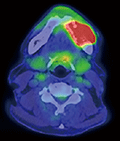

図❹ FDG-PET/CT画像

下顎左側の骨破壊を伴う軟部腫瘤に、高集積(SUVmax18.9)を認める